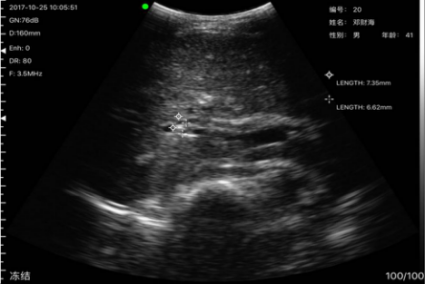

病例7,姓名:罗x姬,性别:女,年龄69岁,发现其胆囊有两亮点疑似胆囊结石,后经上级医院复查确诊为胆囊结石。

胆囊结石与上级医院复诊结果一致

胆囊结石